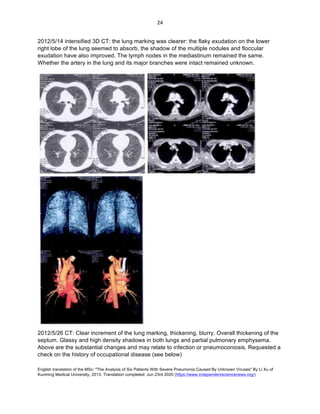

2012/4/25 CT reports: lung markings more numerous and prominent, septal thickening. Multiple

the heart remain normal; no effusion (see below).

2012/4/30 CT reports: Compared to before, the lung markings are more numerous and

nodes in mediastinum. Others unchanged (See below).

2012/5/6 CT: the exudation on the lower right lobe seems to be absorbed, others remained the

mediastinum (See below).

2012/5/14 intensified 3D CT: the lung marking was clearer: the flaky exudation on the lower

exudation have also improved. The lymph nodes in the mediastinum remained the same.

Whether the artery in the lung and its major branches were intact remained unknown.

2012/5/26 CT: Clear increment of the lung marking, thickening, blurry. Overall thickening of the

Above are the substantial changes and may relate to infection or pneumoconiosis. Requested a

check on the history of occupational disease (see below)